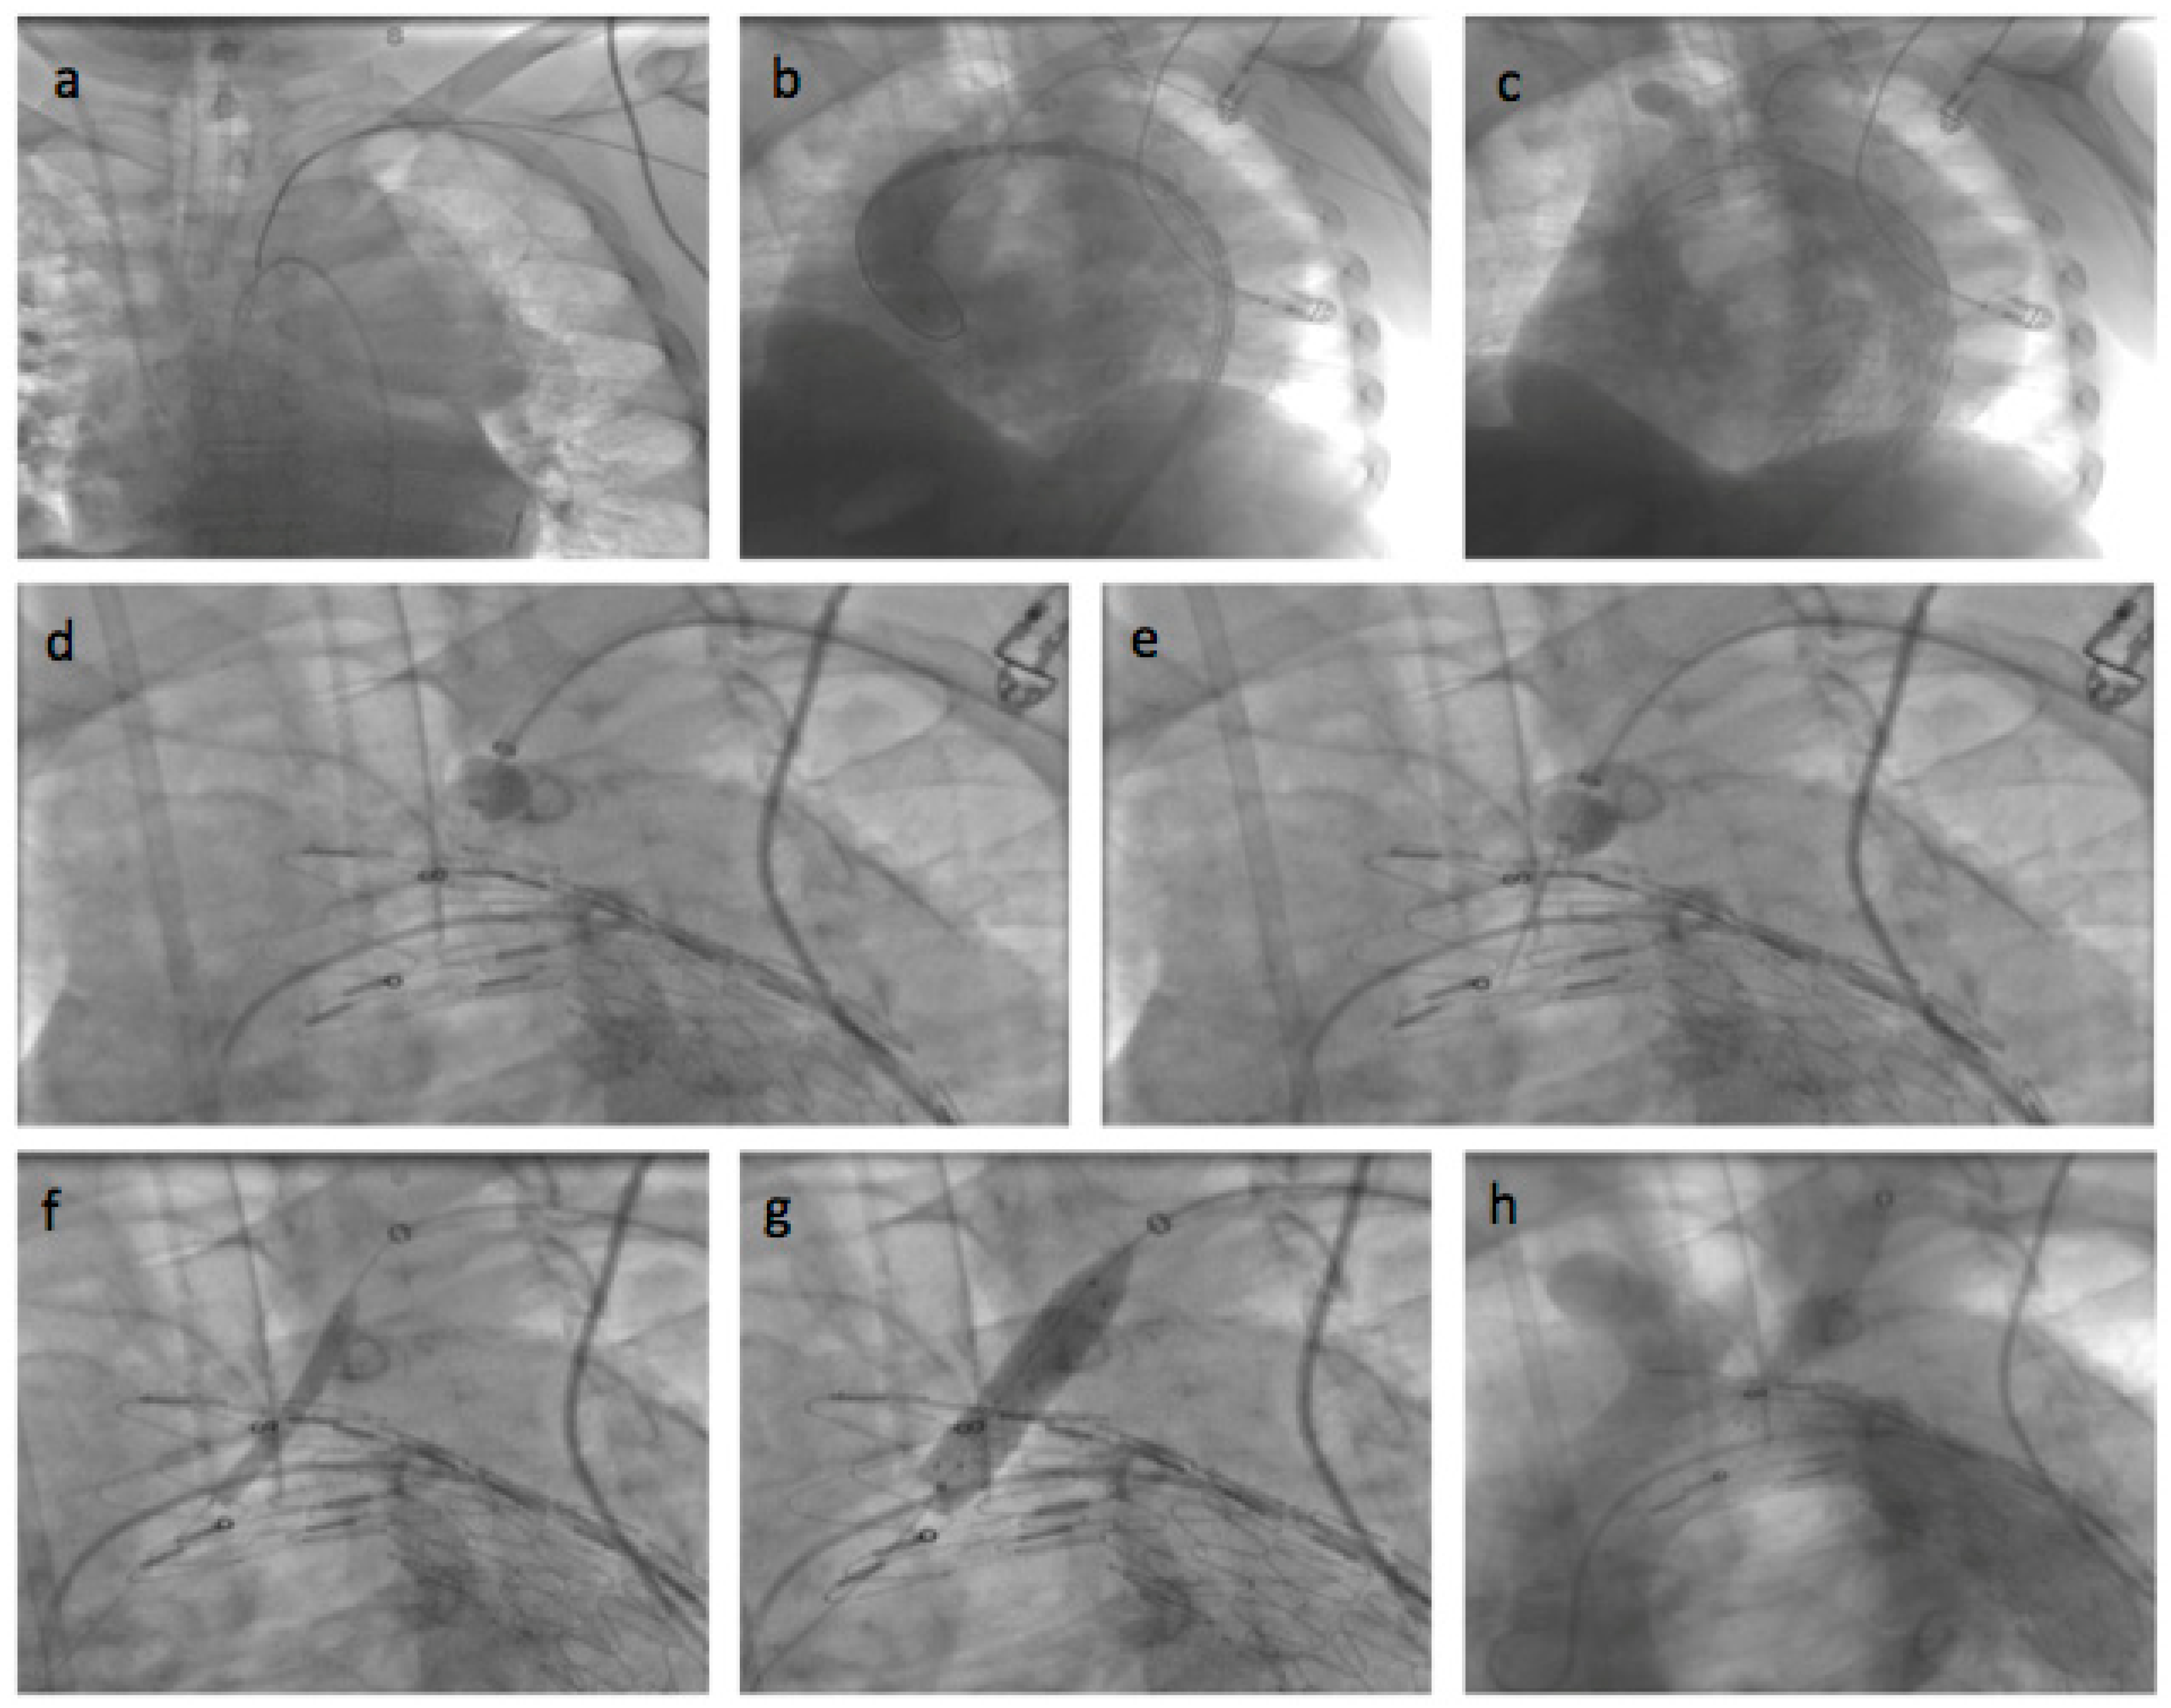

General anesthesia was administered. Vascular access was achieved through the common femoral artery via a cut-down. The FuThrough puncture system (Lifetech Scientific, Shenzhen, China) is designed with a self-centering balloon catheter and an adjustable 20-gauge needle. The puncture system for left subclavian artery (LSA) fenestrations was introduced via the left brachial artery, with an additional cut-down at this site. In situ needle fenestration (ISNF) was initiated following the deployment of the endograft. A steerable sheath (Fustar-Lifetech Scientific, Shenzhen, China) is inserted through the brachial access. The sheath is carefully positioned to be as perpendicular as possible to the greater curvature of the aortic arch, ideally making direct contact with the outer curvature of the thoracic endograft. To ensure stability, the balloon at the tip of the adjustable puncture needle is inflated, with the penetration depth pre-set on the device. The fenestration process involved passing a 0.018 or 0.035 guidewire through the puncture site (advanced into the ascending or descending aorta), which was then widened with a small-sized balloon (4–6 mm). Subsequently, the ISNF is connected with a balloon-expandable chrome cobalt ePTFE stent graft (BeGraft-Bentley, Hechingen, Germany), oversized by about 10%, and potentially antegrade up to 5 mm within the fenestration. The angiographic images during the procedure are shown in Figure 3, and Figure 4 shows the postoperative CT angiography 3D image. The Ankura stent graft was selected for all ISNF group cases due to its properties that facilitate easy puncture and dilatation. This choice was based on its ability to accommodate the technical requirements of ISNF effectively. (Figure 3 and Figure 4).

Figure 3. Angiographic images of left common carotid artery in situ needle fenestration: (a) Guidewire inserted into the ascending aorta; (b) aortic stent graft was advanced in the descending aorta in the unopened state, and the guidewire was retrogradely inserted into the aorta via the brachial artery; (c) the aortic stent graft was placed in the aorta; (d) the in situ needle fenestration puncture system was advanced to the left subclavian artery ostium; (e) the stent graft was punctured with the needle; (f) the fenestration was expanded with a balloon; (g) the stent was implanted in the fenestration; (h) the operation was evaluated with control digital subtraction angiography.